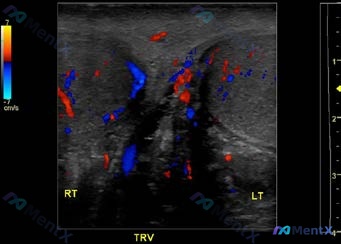

这是一份双侧附睾的多普勒超声对比(纵轴+横轴):

- 右侧(RT):附睾大小形态正常,实质回声均匀,仅见少量点状血流信号。

- 左侧(LT):附睾明显肿大,轮廓饱满,实质回声不均匀(呈低回声伴细小斑点);彩色多普勒显示血流信号显著增多,实质内弥漫性红蓝交织,呈明显充血表现。